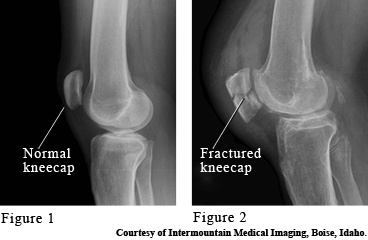

The kneecap (patella) is a bone that protects the front of your knee joint. It takes the brunt of blows to your knee, such as a fall onto a knee or a knee hitting the dashboard. A broken kneecap (fracture) causes swelling and pain, especially when moving the knee back and forth.